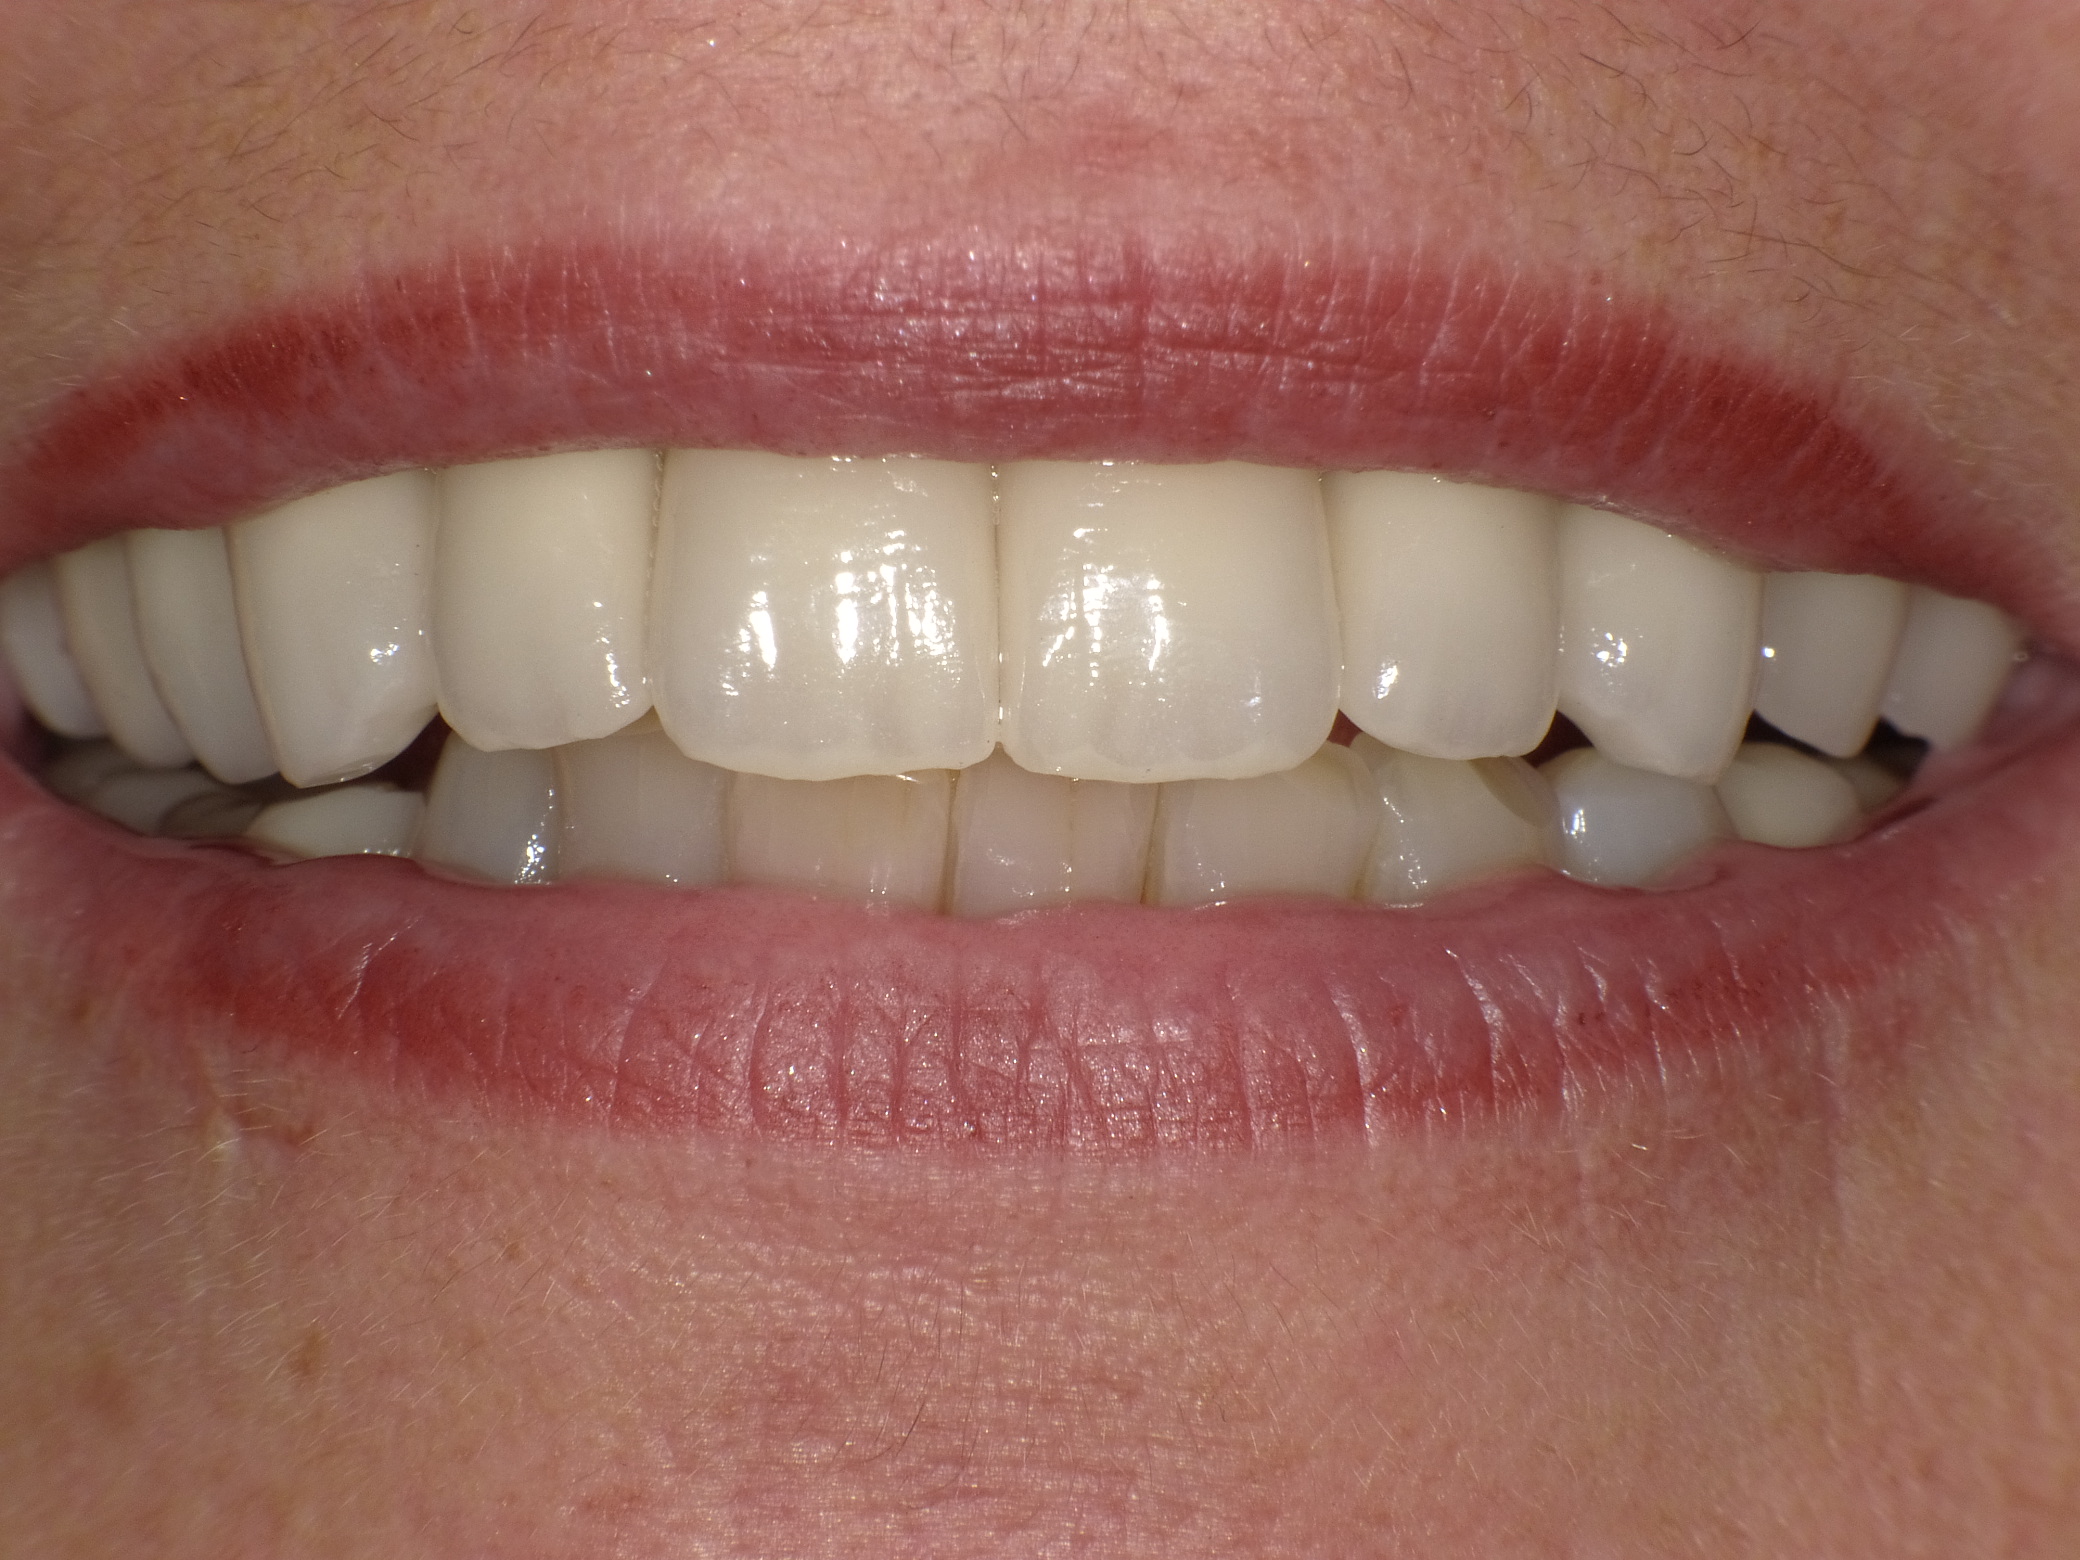

Gesamtbehandlung in Sedierung: die Seitenzähne wurden durch Keramik-Implantate (Zahnentfernungen und Sofortimplantation) mit Knochenaufbau ersetzt; anschließend Gesamtüberkronung aus Vollkeramik mit Optimierung der Ästhetik

Nachher: Gesamtbehandlung in Sedierung: die Seitenzähne wurden durch Keramik-Implantate (Zahnentfernungen und Sofortimplantation) mit Knochenaufbau ersetzt; anschließend Gesamtüberkronung aus Vollkeramik mit Optimierung der Ästhetik